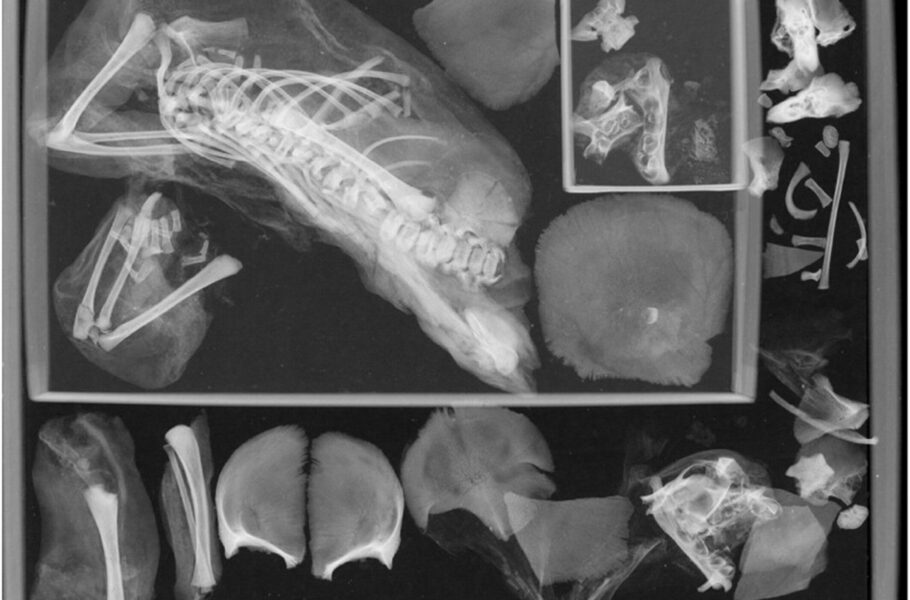

اما بیشتر از یک قرن طول کشید تا باستانشناسان یک جنین دیگر نیز در بدن این مادر مومیاییشده کشف کنند. «فرانسین مارگولیس» (Francine Margolis) تصمیم گرفت به مطالعه دقیقتر این مومیایی موزه اسمیتسونین و بررسی علت مرگش بپردازد. آزمایشهای سیتی اسکن و سپس تصویربرداری اشعه ایکس مشخص کردند که یک جنین دوم نیز در بدن مادر قرار دارد ــ اینبار بهطور اسرارآمیزی در سینه او.

پژوهشگران عقیده دارند که در طی فرایند مومیاییکردن، جنین به بالا و بهسمت سینه مادر جابهجا شده است. بافتهای متصلکننده و دیافراگم در این فرایند از بین میروند، به این ترتیب، جنین میتوانسته به بالا منتقل شود.

Margolis and Hunt, 2023